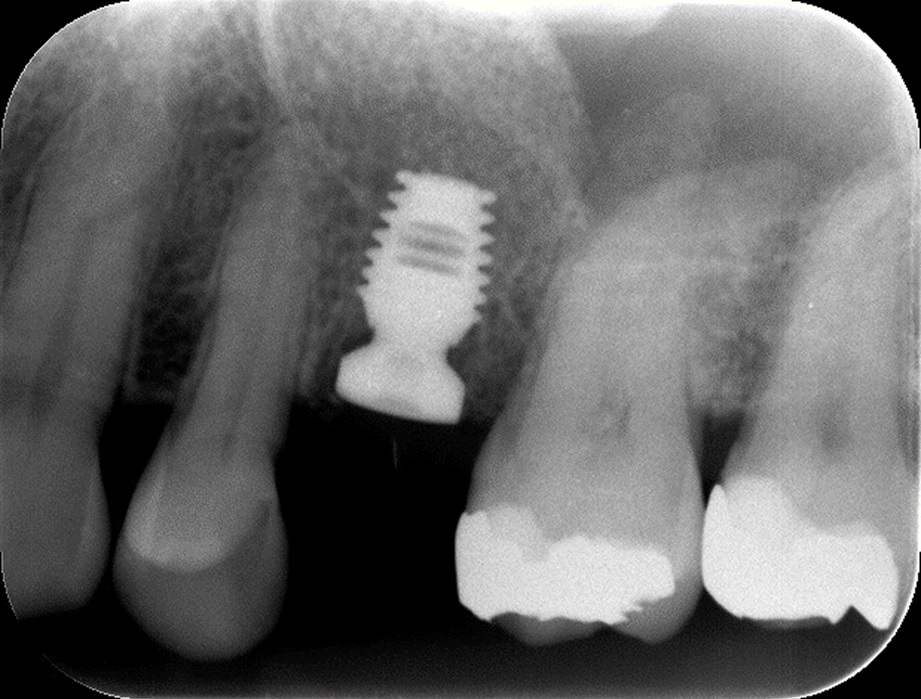

3mm以下になると、骨を作る量が多くなりますので、頬側から窓をあけて横から直接、骨補填剤を入れて骨を作ります。その際、多くのインプラントメーカーが採用するスクリュータイプのインプラントでは、インプラントが完全に固定できず、同時にインプラントを入れてしまうのは難しくなります。長いインプラントを薄い骨で固定すると不安定です。しかし、バイコンというショートインプラントを使用すると頬側に開けた窓から直接、インプラント本体を入れることができることに気づきました。

その方が患者様にとっては、手術回数が2回から1回に減る事になるので、肉体的負担も金銭的負担も減り、きわめて有効であると思います。他のメーカーのインプラントでは、長すぎて入れることができません。

バイコンインプラントが短いからこそできる方法です。